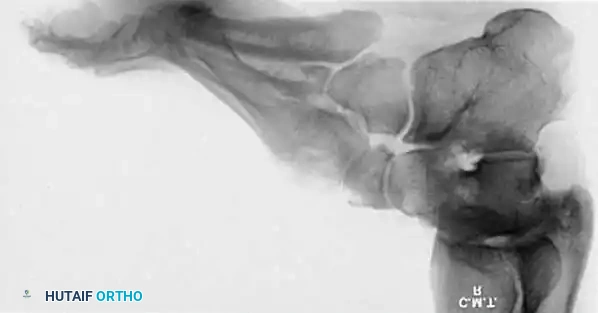

Radiographic Evaluation

Brockway’s 1940 axiom remains true: "Cavus feet should never be operated upon until radiographs with the patient standing have been taken."

Standard weight-bearing anteroposterior (AP) and lateral radiographs of the foot, along with a weight-bearing AP of the ankle, are required.

Key Radiographic Parameters:

* Meary’s Angle (Talus-First Metatarsal Angle): Normally 0 degrees. In a cavus foot, the angle is convex upward (apex dorsal), indicating midfoot/forefoot equinus.

* Calcaneal Pitch: Normally 15 to 20 degrees. In a cavus foot, it is significantly increased (>30 degrees).

* Hibbs Angle: The angle between the longitudinal axis of the calcaneus and the first metatarsal. It approaches 90 degrees in severe cavus (normal is ~140 degrees).

* Talonavicular Coverage: Assessed on the AP view to quantify midfoot adduction.

Fig. 7: Standing lateral radiograph demonstrating an increased calcaneal pitch and a severe apex-dorsal Meary's angle.